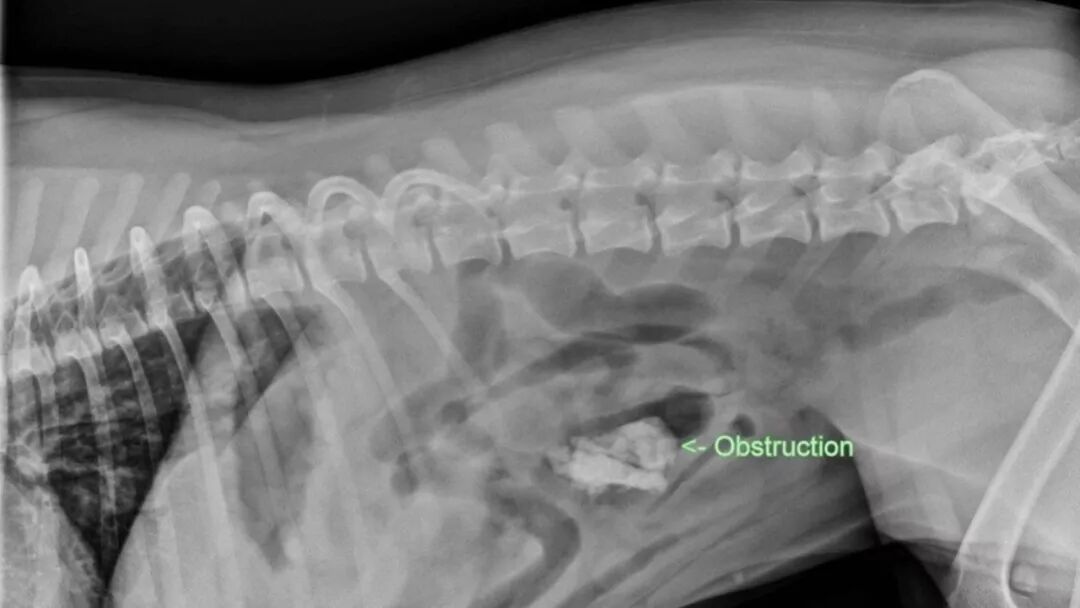

类似的事故也可能发生在宠物身上。今年5月,一位兽医就发出警告,让宠物主人要小心在澳大利亚和新西兰Kmart店出售的一款宠物玩具。

该兽医诊所在其Facebook页面上发出警告,“上周,当地宠物急救中心接连进行了两例狗狗胃肠道清除术,两条狗狗互相并不认识,也无任何关联,清除的肠道阻塞物均是一款$5的Kmart狗咀嚼玩具。”

不过,在Kmart当前的召回名单上,并没有宠物玩具在列。